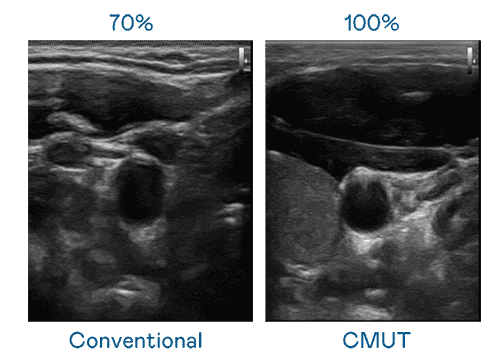

CMUT 技术是一种用电容式微机电元件来产生超音波讯号的技术。。。。与传统 PZT 压电式技术相比,,,,CMUT 频宽增加 30%,,,更宽频的超音波讯号让影像解析度大幅提升,,,,是实现高影像品质医疗超音波扫描、、促进精准医疗发展的关键技术。。。

大频宽带来超清晰影像

超音波影像的解析度高低,,,,首先取决于探头能发出的讯号频宽。。。优游UB8 CMUT 可提供高清晰的超音波讯号,,,提供高频宽、、、、高灵敏度、、、、影像纹理细节更高的超音波影像,,,,协助医护人员缩短影像判读时间及利用精准的医疗影像进行诊断。。。